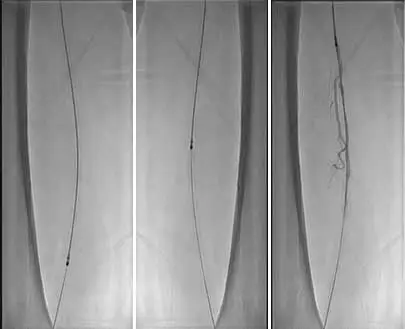

4、減容后,以SABER3mm*30cm球囊預擴張。

5、使用Matrix Super PTX (巴泰醫療)5mm*20cm及5mm*15cm約束型藥物涂層球囊全程擴張左股淺動脈病變。